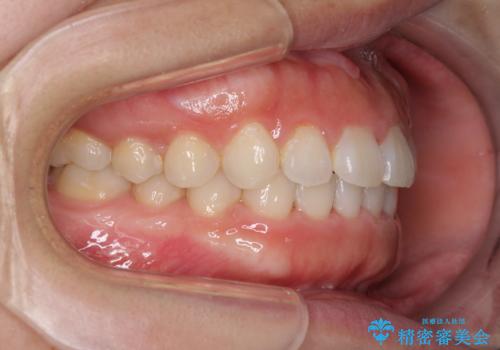

1日22時間の装着時間をしっかり守ってくださったので、1年程度で治療を終えることができました。

1セットのマウスピースで概ね治療を終えたのですが、前歯僅かな叢生が残ったため、2セット目のマウスピースで仕上げました。

気にしていた口元の印象が改善され、患者様には大変満足していただきました。